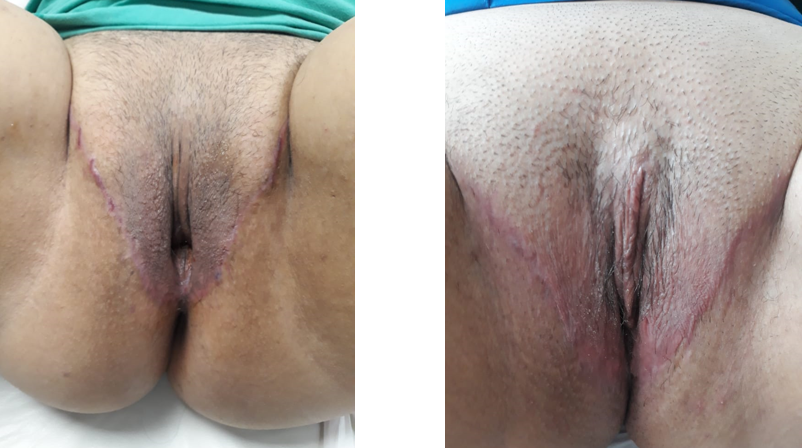

La metoidioplastía se basa en la utilización del clítoris hipertrófico como consecuencia de la terapia hormonal con testosterona tanto sistémica como idealmente tópica. Los tiempos quirúrgicos se pueden programar en un procedimiento único o en más de una cirugía y además se debe considerar que no todo hombre trans desea realizar todos ellos. Estos tiempos quirúrgicos corresponden a: Histerectomía y ooforectomía en los pacientes que no la hayan realizado previamente, colpectomía y colpocleisis, lipectomía suprapúbica y sección del ligamento suspensorio (algunos centros lo evitan para optimizar función eréctil), sección del plateau mucoso ventral para elongar el clítoris y liberar su curvatura, elongación de la uretra desde el meato nativo hasta el glande del clítoris con colgajos de la cara mucosa de los labios menores y posible uso de mucosa oral o vaginal, movilización de colgajos cutáneos para cubrir el neo falo, escrotoplastía y relleno con grasa autóloga o prótesis testiculares.

Las series publicadas reportan resultados con un largo del neo falo de entre 4 y 10cm(8). Estos neo falos presentan resultados estéticos muy satisfactorios, conservan la sensibilidad erógena propia del clítoris y su capacidad eréctil (Figura 6); la actividad sexual penetrativa se logra en una baja proporción de los casos. Las complicaciones que se presentan entre un 10 y un 37% se relacionan principalmente con la elongación de la uretra (fístula y estenosis) o a una cavidad vaginal persistente, generalmente asociado a una fístula en la unión entre la uretra nativa y la elongación uretral(8) .